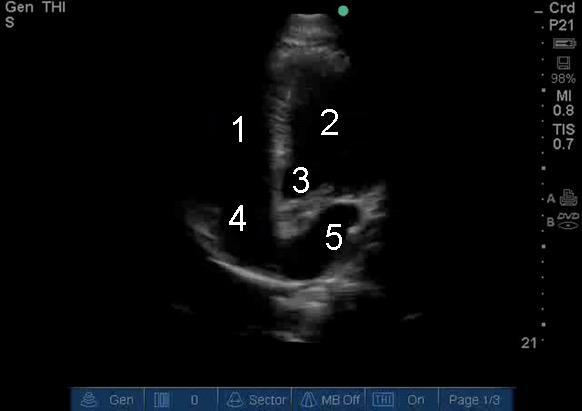

Heart Apical 5 Chamber View 2 Image

1. Right Ventricle (RV)

2. Left Ventricle (LV)

3. Aorta

4. Right Atrium (RA)

5. Left Atrium (LA)